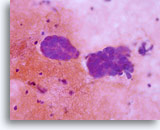

Abnorme Endometriumzellen (NOS)

(51-jährige Patientin, perimenopausal) Neben einzeln liegenden reifen Plattenepithelzellen findet sich ein kleiner, dreidimensionaler Drüsenzellverband. Das Zytoplasma weist multiple, gut erkennbare Vakuolen auf. Die Zellen haben sich abgerundet und die Kerne sind rund bis oval mit klarem Chromatinmuster.

40x

Biopsie – Benignes proliferierendes Endometrium

Abnorme Endometriumzellen (NOS)

(51-jährige Patientin, perimenopausal) Neben einzeln liegenden reifen Plattenepithelzellen findet sich ein kleiner, dreidimensionaler Drüsenzellverband. Das Zytoplasma weist multiple, gut erkennbare Vakuolen auf. Die Zellen haben sich abgerundet und die Kerne sind rund bis oval mit klarem Chromatinmuster.

40x

Biopsie -Benignes proliferierendes Endometrium